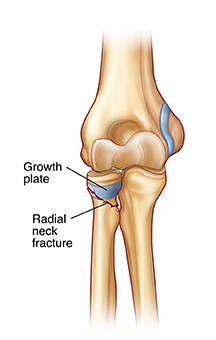

| Radial neck fracture. |